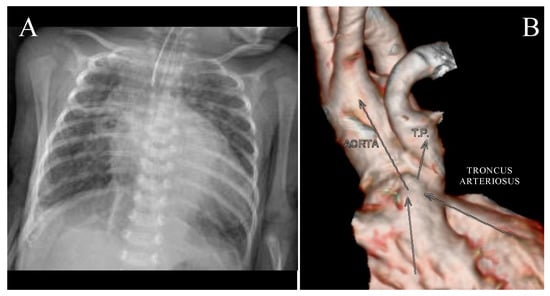

Clinical description of a positive 22q11.2DS patient: A 6-month-old girl, a product of a healthy, non-consanguineous couple with a previous abortion with an unknown diagnosis, was referred to the pediatric cardiology department with cardiogenic shock and sepsis. Chest roentgenography showed grade III cardiomegaly and right lung congestion. An electrocardiogram showed biventricular hypertrophy and left atrial enlargement. An echocardiogram showed situs solitus, patent foramen ovale, truncus arteriosus, emergence override by 60%, and ventricular septal defect of 9 × 7 mm. Angiotomography showed four chamber enlargement, 12.4 mm ventricular septal defect, truncus arteriosus type I, and pulmonary stenosis (Figure 3).

Figure 3. Patient positive for 22q11.2 microdeletion syndrome: (A) Chest roentgenography showing grade III cardiomegaly and right lung congestion; (B) angiotomography showing truncus arteriosus type I and pulmonary stenosis.